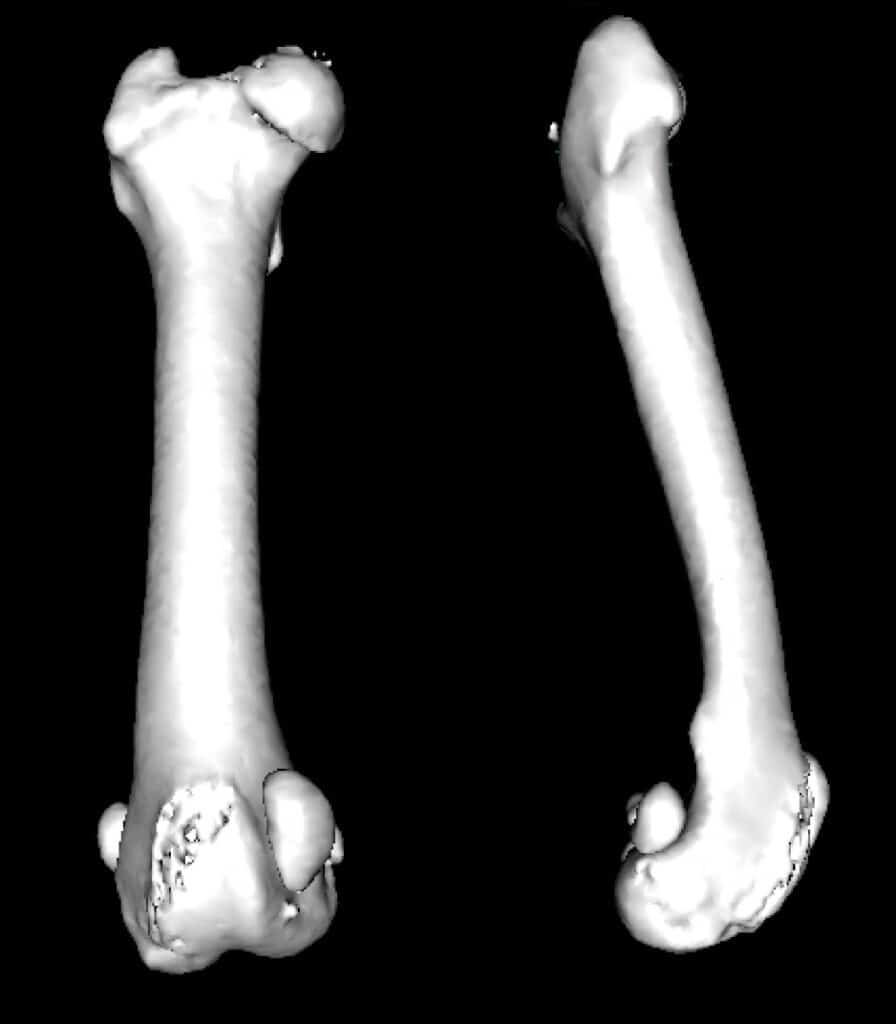

Un bilan radiographique ou scanner est réalisé en préopératoire et permet d’évaluer les corrections chirurgicales à réaliser. Le bilan scanner est plus précis et sera préconisé dans les cas les plus complexes. Le bilan radiographique nécessite une sédation profonde pour réaliser a minima 5 vues radiographiques très précises (face et profil du tibia et du fémur, vue axiale du fémur pour évaluer l’anteversion). Dans le cas du bouledogue, les mesures effectuées sur les reconstructions 3D du scanner mettent en évidence une torsion fémorale externe (angle d’anteversion nul à 0°), ainsi qu’un varus fémoral de 14° également (+10°).